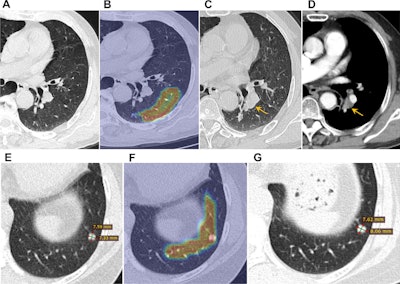

Case-based visualization of model predictions and heatmap analysis for lung cancer risk assessment in baseline nodule-free and nodule-existing examples. (A-D) Images in a 68-year-old man with a 96 pack-year smoking history and no history of respiratory disease. (A) There are no visible nodules in the left lower lobe at baseline chest low-dose CT. (B) Corresponding baseline heatmaps from the peripheral lung parenchyma where a tumor subsequently developed. Regions highlighted in red indicate areas with a stronger positive contribution to the predicted outcome, whereas regions in blue indicate areas with minimal contribution (ScreenLungNet risk 0.77). (C) Lung window and (D) contrast-enhanced mediastinal window images obtained 14.1 months after the baseline scan reveal a mass adjacent to the left lower hilar region (arrow). Subsequent bronchoscopy and biopsy confirmed the diagnosis of squamous cell carcinoma. (E-G) Images in a 63-year-old woman without a smoking history or respiratory disease. (E) Baseline chest low-dose CT image shows a solid nodule with a mean diameter of 7.5 mm in the left lower lobe (Lung CT Screening Reporting and Data System 3). (F) Corresponding baseline heatmap shows the model’s focus on the nodule and surrounding features (ScreenLungNet risk 0.98). (G) Follow-up images obtained 5.1 months after the baseline scan reveals nodule growth to a mean diameter of 7.8 mm. Subsequent surgical pathologic examination confirmed the diagnosis of mucinous adenocarcinoma. Images and caption courtesy of the RSNA.Case-based visualization of model predictions and heatmap analysis for lung cancer risk assessment in baseline nodule-free and nodule-existing examples. (A-D) Images in a 68-year-old man with a 96 pack-year smoking history and no history of respiratory disease. (A) There are no visible nodules in the left lower lobe at baseline chest low-dose CT. (B) Corresponding baseline heatmaps from the peripheral lung parenchyma where a tumor subsequently developed. Regions highlighted in red indicate areas with a stronger positive contribution to the predicted outcome, whereas regions in blue indicate areas with minimal contribution (ScreenLungNet risk 0.77). (C) Lung window and (D) contrast-enhanced mediastinal window images obtained 14.1 months after the baseline scan reveal a mass adjacent to the left lower hilar region (arrow). Subsequent bronchoscopy and biopsy confirmed the diagnosis of squamous cell carcinoma. (E-G) Images in a 63-year-old woman without a smoking history or respiratory disease. (E) Baseline chest low-dose CT image shows a solid nodule with a mean diameter of 7.5 mm in the left lower lobe (Lung CT Screening Reporting and Data System 3). (F) Corresponding baseline heatmap shows the model’s focus on the nodule and surrounding features (ScreenLungNet risk 0.98). (G) Follow-up images obtained 5.1 months after the baseline scan reveals nodule growth to a mean diameter of 7.8 mm. Subsequent surgical pathologic examination confirmed the diagnosis of mucinous adenocarcinoma. Images and caption courtesy of the RSNA.